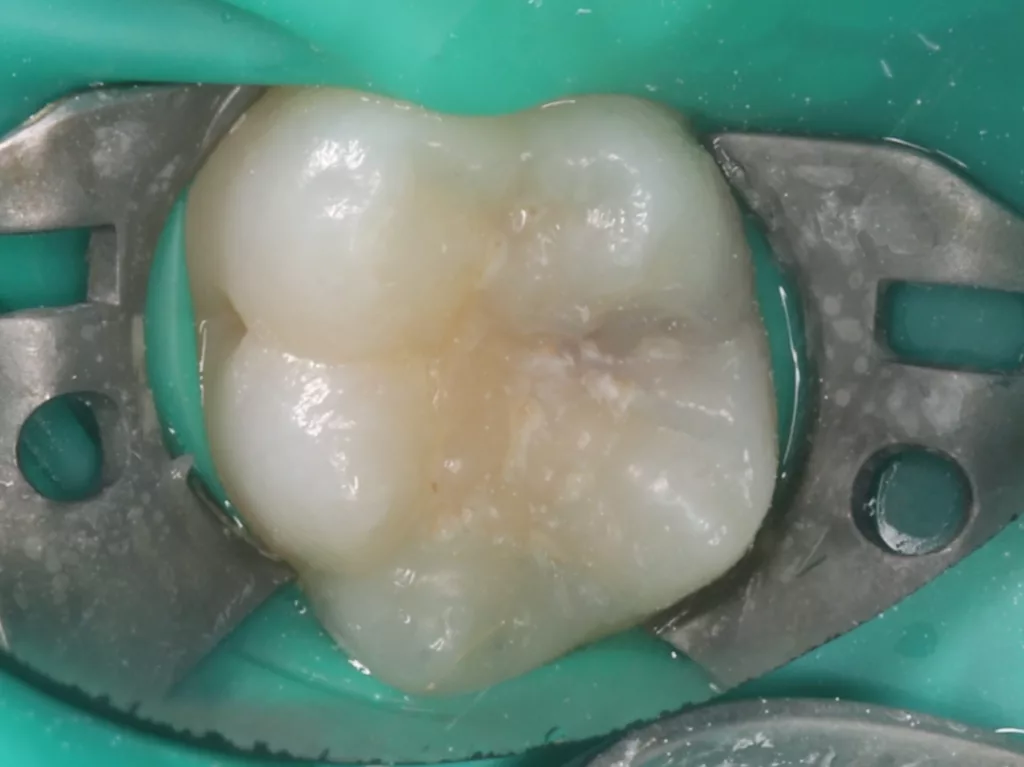

Unter Lokalanästhesie mit dem STA-System (Milestone Scientific, USA) und Septanest 1/200 000 (Septodont, Frankreich) wurde die überstehende Gingiva mit dem Khors Koagulator (Эctatex, Ukraine) koaguliert und der Bereich unter Kofferdam kontaminationsfrei dargestellt (Klammer U67, KSK Dentech, Japan). Die schmalen Fissuren wurden mit dem Fissurenbohrer CD-53F (Mani, Japan) erweitert, um anschließend mittels RONDOflex plus 360 (KaVo Dental, Deutschland) und Pulver 27 µm vollständig gereinigt werden zu können. Es konnte weder durch visuelle Inspektion noch Sondierung mit 0.08 H-file (Mani, Japan) ein Defekt des Zahnschmelzes festgestellt werden. Unter Berücksichtigung der Integrität des Zahnschmelzes, der Symptomlosigkeit, des Behandlungszeitpunktes, Alters des Kindes und Wachstums der Zahnwurzeln fiel gemeinsam mit den Eltern die Wahl auf eine konservative Therapie. Es wurde eine Fissurenversiegelung mit Clinpro Sealant (3M, USA) unter Anwendung eines adhäsiven Behandlungsprotokolls mit Optibond FL (Kerr, USA) durchgeführt. Dieser klinische Fall ist dahingehend einzigartig, da alle anderen ersten und zweiten Molaren des Kindes ebenso von einer PEIR betroffen waren (Grad 1 bis 2 der Läsion nach Seow) (Abb. 3 und 12). Normallerweise ist nur ein Zahn bei einer Patientin oder einem Patienten betroffen. Die Zahnkronen der anderen betroffenen Zähne erwiesen sich bei der klinischen Untersuchung als intakt; die radioluzenten Läsionen innerhalb des koronalen Dentingewebes waren wesentlich kleiner als die von Zahn 36. Daher wurde auch bei diesen Molaren das gleiche Behandlungsprotokoll angewendet und nur eine Fissurenversiegelung durchgeführt.

Im Rahmen der jährlichen Kontrolluntersuchung wurde bei einem achtjährigen Mädchen auf der routinemäßig angefertigten Röntgenaufnahme eine mittelgroße PEIR des Zahnes 46 (Grad 2 der Läsion nach Seow) entdeckt (Abb. 43). Die Patientin war komplett beschwerdefrei und der Zahnschmelz des betroffenen Zahnes sah intakt aus (Abb. 44 und 45). Weil auch hier der PEIR-Defekt gräulich durchschimmerte (Abb. 44 und 45) und der Zahn bereits seit einem Jahr durchgebrochen war, entschieden wir uns in diesem Fall, den Defekt klassisch mit Komposit zu restaurieren. Unter Lokalanästhesie mit Septanest 1/100 000 (Septodont, Frankreich) wurde zunächst Kofferdam mithilfe der Klammer U67 (KSK Dentech, Japan) gelegt (Abb. 45). Weder visuell noch mittels Sondierung konnte eine Verbindung zur Läsion festgestellt werden. Deswegen wurde an der Stelle, an welcher der PEIR-Defekt gräulich schimmerte, intakter Zahnschmelz der lingualen Querfissur entfernt (Abb. 46). Innerhalb der Läsion wurde nekrotisches intrakoronales Weichgewebe vorgefunden (Abb. 47), das problemlos mittels RONDOflex plus 360 (KaVo Dental, Deutschland) mit dem 27-µm-Pulver vollständig entfernt werden konnte. Der Boden des Defektes zeigte eine glatte, runde Form sowie helles, hartes und intaktes Dentin. Eine Präparation war nicht erforderlich, es wurde lediglich die Zahnschmelzkante geglättet (Abb. 48). Für die Restauration kamen erneut das Adhäsiv Optibond FL (Kerr, USA) und das Komposit Estelite ASTERIA OCE, A2B und Universal Flow AO2 (Tokuyama, Japan) zur Anwendung (Abb. 49). 6 Monate nach der Behandlung zeigte sich das Ergebnis sowohl aus klinischer als auch radiologischer Sicht stabil wie die Abbildungen 50 und 51 zeigen.